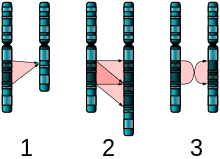

In the genetic area, relations have been found between autism and schizophrenia based on duplications and deletions of chromosomes; research showed that schizophrenia and autism are significantly more common in combination with 1q21.1 deletion syndrome. Research on autism/schizophrenia relations for chromosome 15 (15q13.3), chromosome 16 (16p13.1) and chromosome 17 (17p12) are inconclusive.[101]